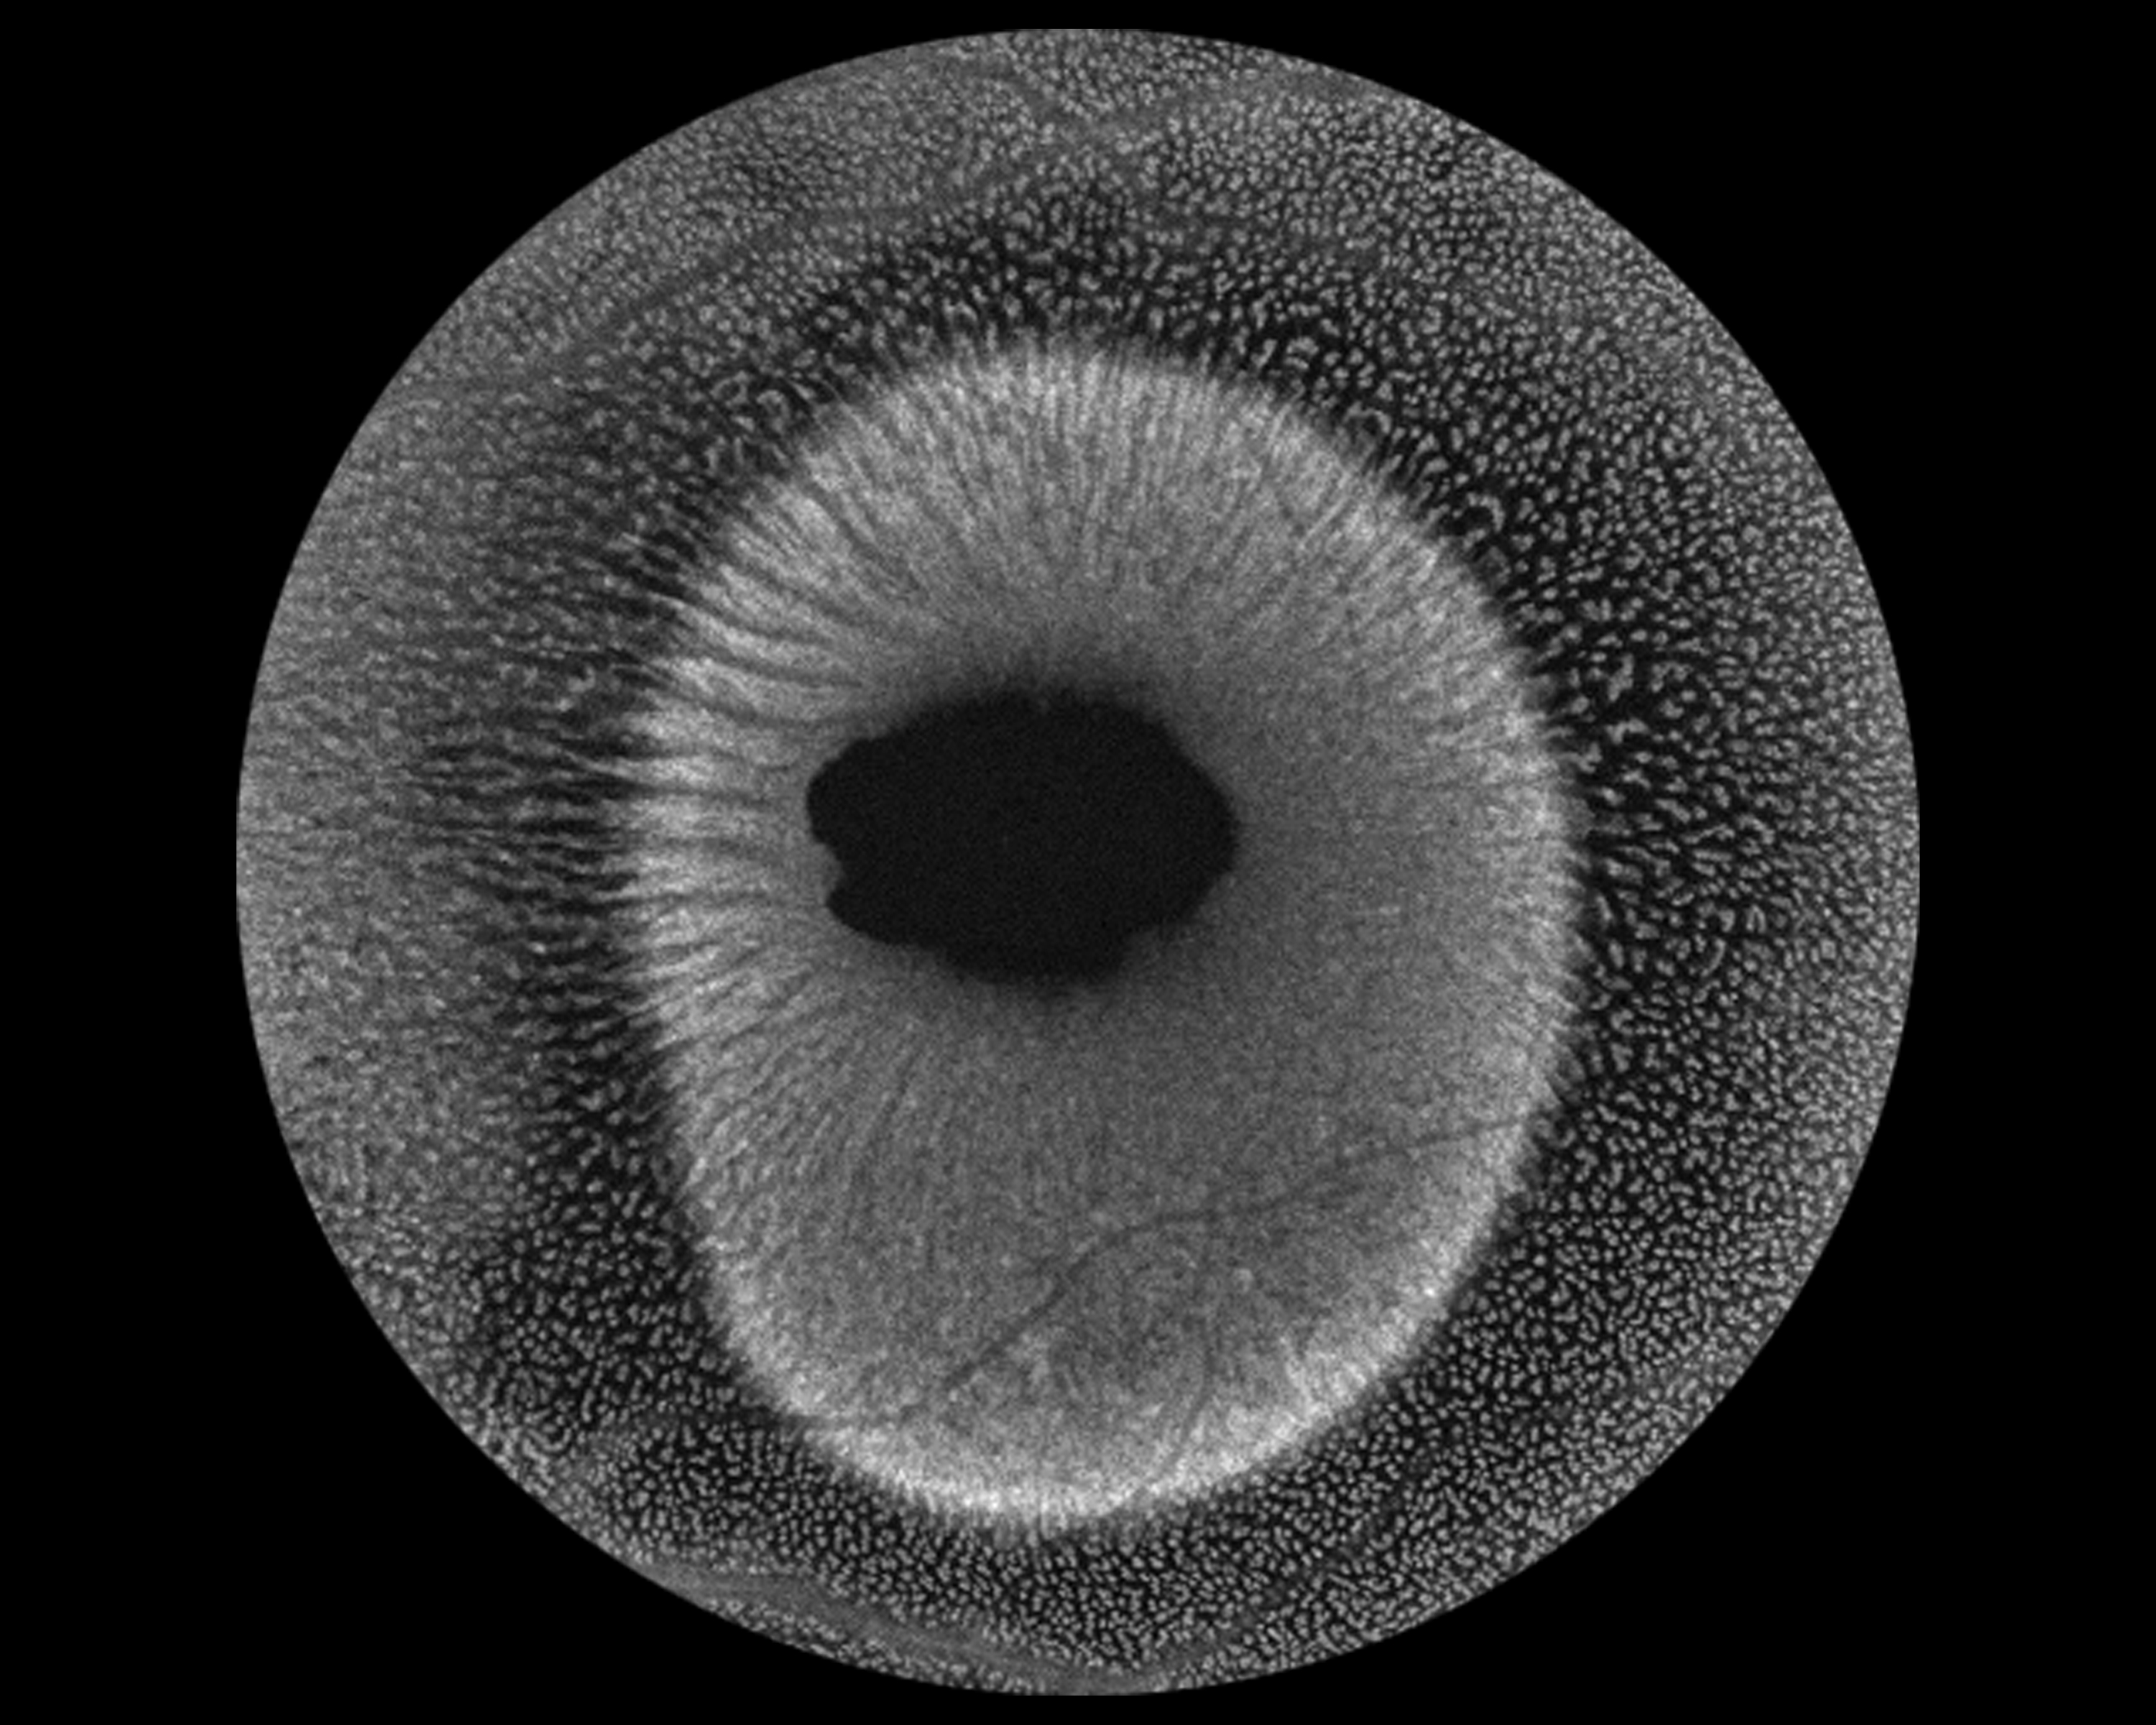

Macular Schisis Presented by Kasi Sandhanam This photograph received Best in Show - Stereo in the 2025 OPS Scientific Exhibit. Filed Under Retina OPS Photo